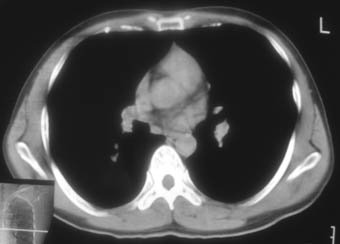

锁骨骨折复查,发现肺内高密度影,行ct检查。

男性,35岁,无任何感觉,无明显发热感冒病史。

纵隔窗!

右肺下叶背段斑片状阴影,边缘模糊,纵隔内未见肿大淋巴结,病人无发热及感冒史,要考虑浸润型肺结核,可结合ppd检查,或短期抗炎治疗复查。

右肺下叶背段长椭圆型病灶,边缘较规则,无明显分叶征、毛刺,远段未见阻塞征象,病灶较松散,纵隔窗明显小于肺窗,年龄35岁,支气管稍示变窄,纵隔内未见明显肿大淋巴结,这些都不支持肿瘤。病人无任何感觉,无明显发热感冒病史,首先考虑结核(也是结核好发部位),慢性炎症不能完全除外。